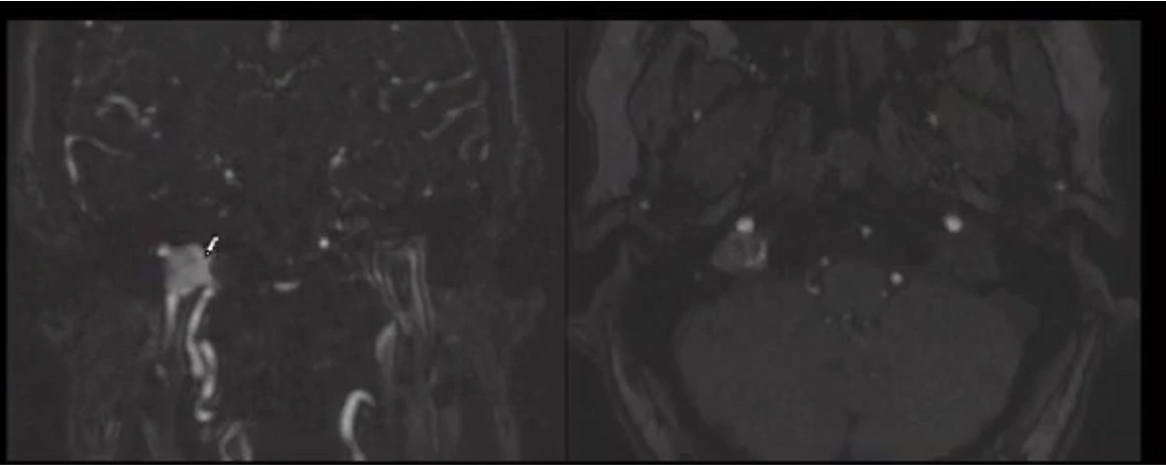

glomus jugulare

endolymphatic sac tumor. associated with VHL

what percent of VHL patients get endolymphatic sac tumors

15%